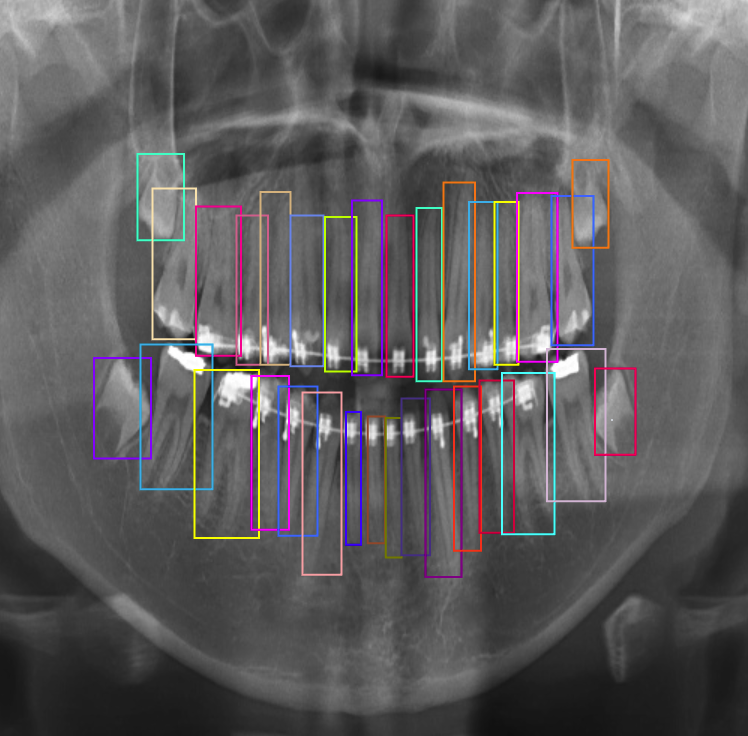

Due to the lack of image labels necessary for training models in the presented dataset, we initially labelled 425 images from the set. We collected two sets of basic annotations, for instance segmentation and object detection respectively. We selected these 425 images randomly from all categories and maintained same distribution of images across all categories as in the original dataset. For manual labelling, we chose the semi-automated annotation tool Roboflow [28] for bounding box annotations needed for the objection detection task. We also used another annotation tool, Apeer [29], to help us create individual segmentation masks for each of the 32 teeth in the images in the dataset. These binary masks provided additional information by focusing on the fine contours and boundaries of the teeth. We converted the resulting segmented polygons into binary maps of size 512×\times512×\times32. This comprehensive approach to annotation was pivotal in ensuring our model’s success in dental image analysis. An example of annotations is shown in Fig. 2.

Refer to caption

Figure 2: (a) Annotated polygon mask. (b) Annotated bounding Box scan. (c) Binary mask of polygon-based annotation